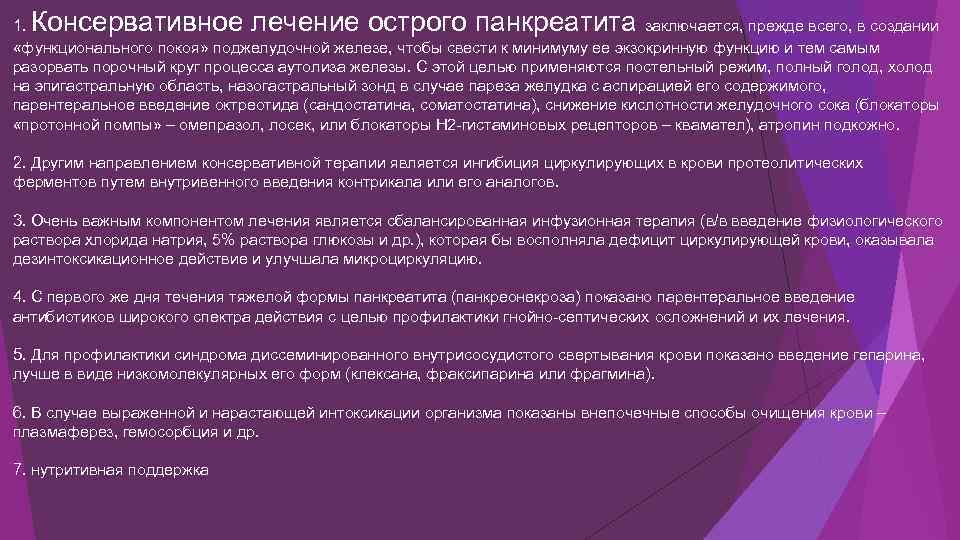

Консервативное лечение острого панкреатита 1. заключается, прежде всего, в создании «функционального покоя» поджелудочной железе, чтобы свести к минимуму ее экзокринную функцию и тем самым разорвать порочный круг процесса аутолиза железы. С этой целью применяются постельный режим, полный голод, холод на эпигастральную область, назогастральный зонд в случае пареза желудка с аспирацией его содержимого, парентеральное введение октреотида (сандостатина, соматостатина), снижение кислотности желудочного сока (блокаторы «протонной помпы» – омепразол, лосек, или блокаторы Н 2 -гистаминовых рецепторов – квамател), атропин подкожно. 2. Другим направлением консервативной терапии является ингибиция циркулирующих в крови протеолитических ферментов путем внутривенного введения контрикала или его аналогов. 3. Очень важным компонентом лечения является сбалансированная инфузионная терапия (в/в введение физиологического раствора хлорида натрия, 5% раствора глюкозы и др. ), которая бы восполняла дефицит циркулирующей крови, оказывала дезинтоксикационное действие и улучшала микроциркуляцию. 4. С первого же дня течения тяжелой формы панкреатита (панкреонекроза) показано парентеральное введение антибиотиков широкого спектра действия с целью профилактики гнойно-септических осложнений и их лечения. 5. Для профилактики синдрома диссеминированного внутрисосудистого свертывания крови показано введение гепарина, лучше в виде низкомолекулярных его форм (клексана, фраксипарина или фрагмина). 6. В случае выраженной и нарастающей интоксикации организма показаны внепочечные способы очищения крови – плазмаферез, гемосорбция и др. 7. нутритивная поддержка

Консервативное лечение острого панкреатита 1. заключается, прежде всего, в создании «функционального покоя» поджелудочной железе, чтобы свести к минимуму ее экзокринную функцию и тем самым разорвать порочный круг процесса аутолиза железы. С этой целью применяются постельный режим, полный голод, холод на эпигастральную область, назогастральный зонд в случае пареза желудка с аспирацией его содержимого, парентеральное введение октреотида (сандостатина, соматостатина), снижение кислотности желудочного сока (блокаторы «протонной помпы» – омепразол, лосек, или блокаторы Н 2 -гистаминовых рецепторов – квамател), атропин подкожно. 2. Другим направлением консервативной терапии является ингибиция циркулирующих в крови протеолитических ферментов путем внутривенного введения контрикала или его аналогов. 3. Очень важным компонентом лечения является сбалансированная инфузионная терапия (в/в введение физиологического раствора хлорида натрия, 5% раствора глюкозы и др. ), которая бы восполняла дефицит циркулирующей крови, оказывала дезинтоксикационное действие и улучшала микроциркуляцию. 4. С первого же дня течения тяжелой формы панкреатита (панкреонекроза) показано парентеральное введение антибиотиков широкого спектра действия с целью профилактики гнойно-септических осложнений и их лечения. 5. Для профилактики синдрома диссеминированного внутрисосудистого свертывания крови показано введение гепарина, лучше в виде низкомолекулярных его форм (клексана, фраксипарина или фрагмина). 6. В случае выраженной и нарастающей интоксикации организма показаны внепочечные способы очищения крови – плазмаферез, гемосорбция и др. 7. нутритивная поддержка